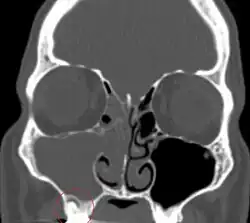

The diagnosis of odontogenic sinusitis is often challenging and requires a multidisciplinary approach involving otolaryngologists and dental specialists. Clinical examination and patient history play a crucial role.[11] Radiological investigation, including dental panoramic radiographs, computed tomography scans, and cone-beam computed tomography can help visualize the relationship between the maxillary sinuses and the dental structures, identify dental pathologies, and assess the extent of sinus involvement.[1]